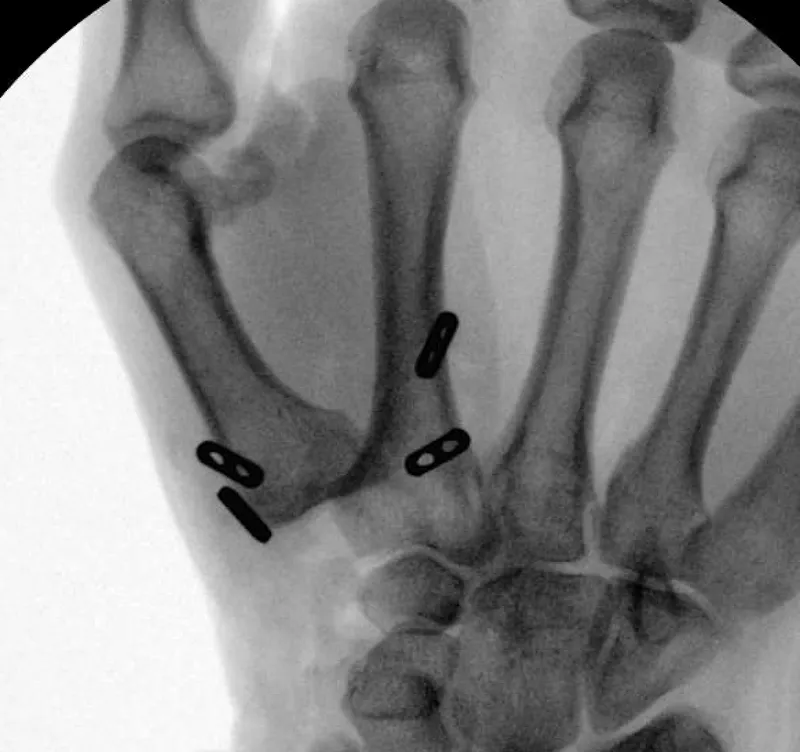

- Arthroplasty: MCP (silicone most common), PIP, Wrist.

⭐ MCP joint arthroplasty is preferred over fusion to preserve motion, crucial for hand function.